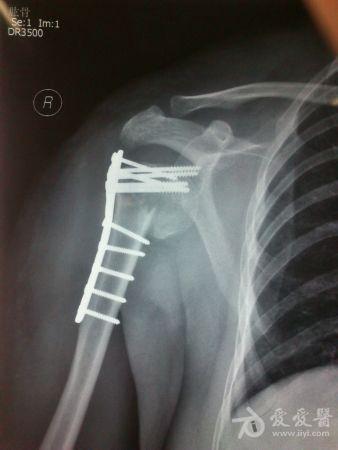

病史特点及病情摘要:1、患者女性,51岁。2、患者自诉入院前1年余因右肱骨外科颈骨折在外院行切开复位内固定术,术后右肩关节疼痛、活动受限,一直未予处理,今为明确诊治入院。患者精神、食欲、睡眠尚可。3、既往史、个人史、家族史无特殊。4、入院查体:生命征平稳,心肺腹检查未见异常,NS(-)。专科情况:右上臂近端内侧见一约15cm手术切口疤痕,愈合佳,右肩关节能外展20度,前屈、后伸及旋前、旋后功能障碍,余关节活动好。舌质红,苔薄白,脉实。5、辅助检查:右肩关节正侧位片:右肱骨外科颈骨折内固定术后再骨折伴右肩关节脱位。

诊断:右肱骨外科颈骨折内固定术后再骨折伴右肩关节脱位

诊疗计划:????前两张片是院外术前,中间两张是院外术后,后两张是在我院照。 术前

我院门诊

同意楼主观点,患者第一次手术复位欠佳,但可勉强接受。但钉子穿出,是手术后肩关节疼痛的主要原因,现在看骨折已愈合,头无明显头坏死迹象,只需取出内固定,麻醉下活动肩关节,使肩关节活动度改善,术后加强功能锻炼,应该恢复不错。

是的,就这样了:帮忙取出了内固定物,病人是没有什么不满意的理由的.后期,让病人循序渐进地进行肩关节的功能锻炼,避免再次骨折,